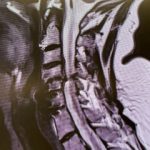

Current imaging studies (Figs. 1 and 2) demonstrated significant degenerative collapse of C45 segment, retrolisthesis and with severe right foraminal stenosis as well as C3-4 degenerative disc degeneration with moderate compression of thecal sac. Patient failed conservative management and it was decided, given her prior two anterior procedures, that an excellent decompression could be accomplished with a posterior laminectomy, foraminotomy and fusion to maintain alignment.

(Fig. 1) Sagittal T2 cervical MRI demonstrates significant C34 and C45 disc degeneration and osteophyte formation and instability status post anterior cervical discectomy and fusion C5-C7.